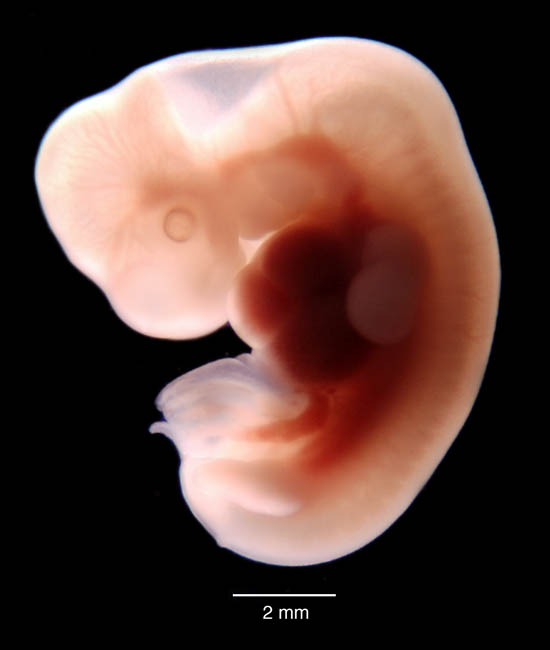

Эмбрион 6 7 Недель ФотоВыберите Ваш пол👨 👉🏻👉🏻👉🏻МУЖЧИНА👈🏻👈🏻👈🏻👩🦱 👉🏻👉🏻👉🏻ЖЕНЩИНА👈🏻👈🏻👈🏻Эмбрион 6 7 Недель Фото (132 фото)